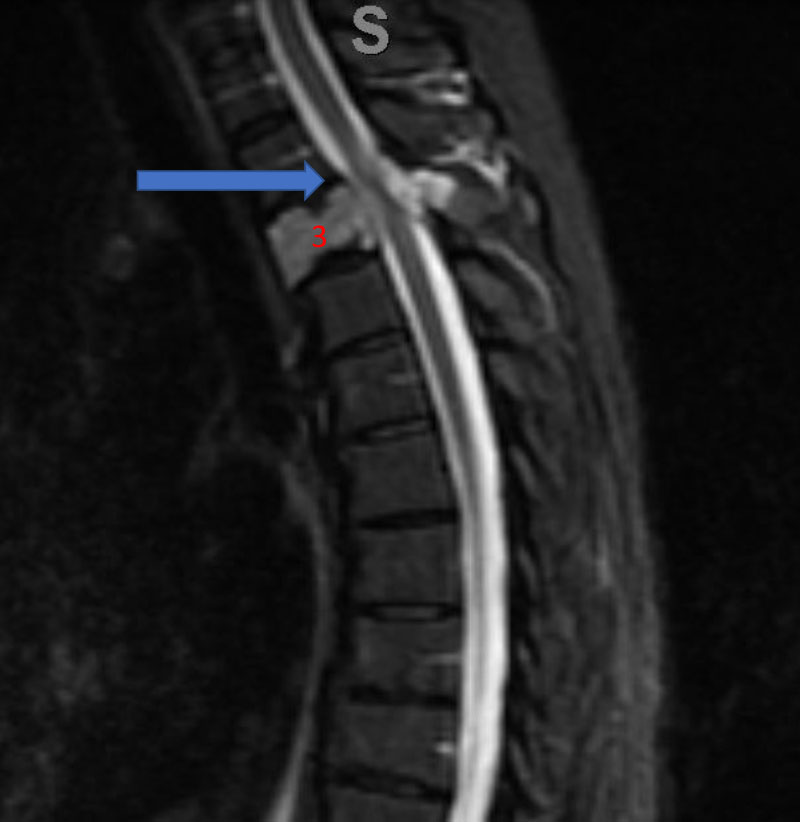

He presented to the emergency room with a one-week history of thoracic pain in addition to bilateral lower extremity weakness and paraparesis. MRI imaging with contrast showed a diffuse abnormal signal within the vertebral body of T3 and the posterior elements with lobulated soft tissue lesion extension into both paraspinal areas (Figure 1. A, B, C).

Figure 1. A) Sagittal T2 MRI demonstrates aggressive hyperintense T3 hemangioma involving the body and posterior elements compressing the thoracic spinal cord (arrows)